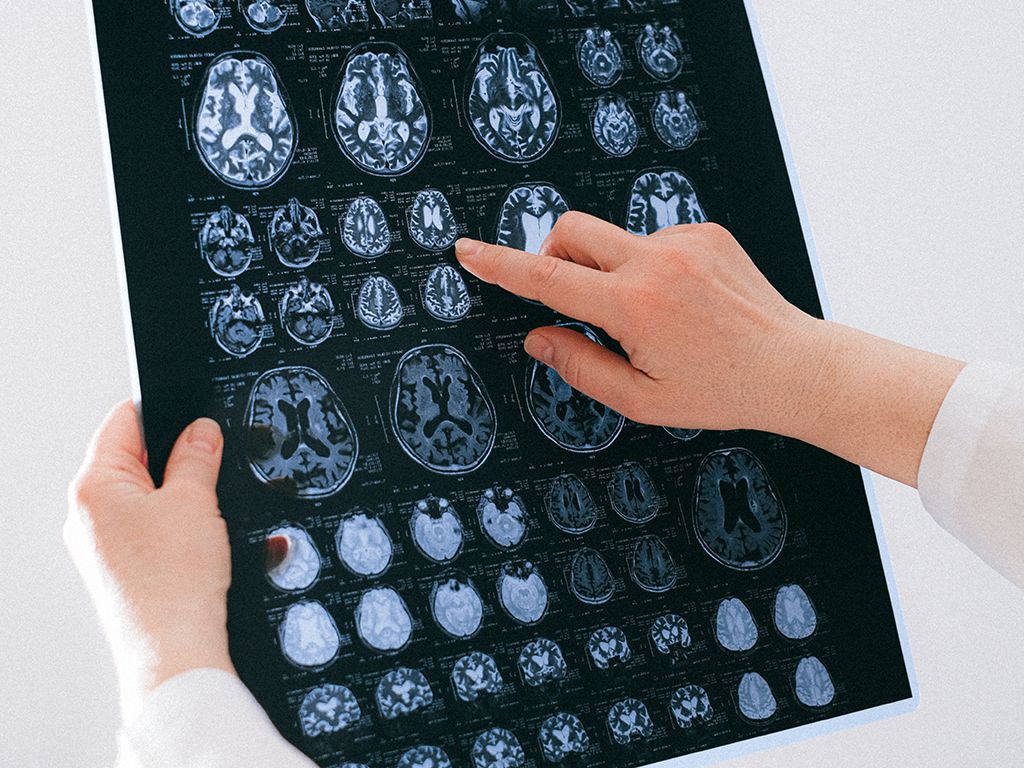

I’ve always had headaches, almost daily. About 10 years ago, I started seeing weird auras that would take up my whole vision, and then I’d get a terrible headache that would make me want to end it all. Maybe once a year that would happen.

About three years ago, we got really good insurance. Then, I got several auras in a row, and I started to worry that it was a detached retina or something.

So I went to an ophthalmologist, who dilated my eyes and looked around. He suggested I see a neurologist, and maybe they’d do an MRI. Meanwhile, I had a stomach ache that lasted for a few days—very odd for me, since I don’t really get them.

But it woke me up in the middle of the night, and I had another aura visual—but no headache.

I saw the neurologist a week later and boy did he like talking about how fat I was. I had three kids in three years, so naturally, I became squishy—not morbidly obese, but I did have some mobility issues. Deal with it. They were able to get me in for the MRI that day, and despite being claustrophobic, it wasn’t terrible.

I walked out to the parking lot, and they called me back in. When I got in, she told me I’d had a stroke, and they needed to admit me to the ER. The office was at the hospital already, so she literally just walked me through like two doors, and I didn’t even have to wait in the lobby.

I spent three days being poked and prodded. I never really saw the big deal, it was just a stomach ache and dancing lights. I’m doing a lot better now.